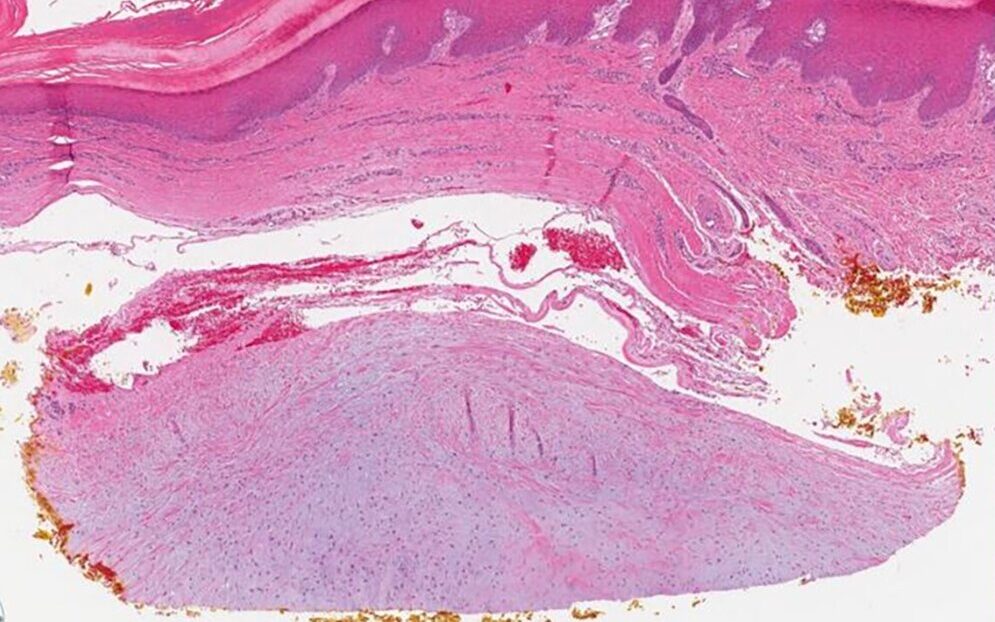

W celu potwierdzenia diagnozy konieczne może być wykonanie badania histopatologicznego, polegającego na pobraniu fragmentu tkanki i jego analizie pod mikroskopem. Pozwala to odróżnić zmianę łagodną od innych, potencjalnie groźniejszych zmian.